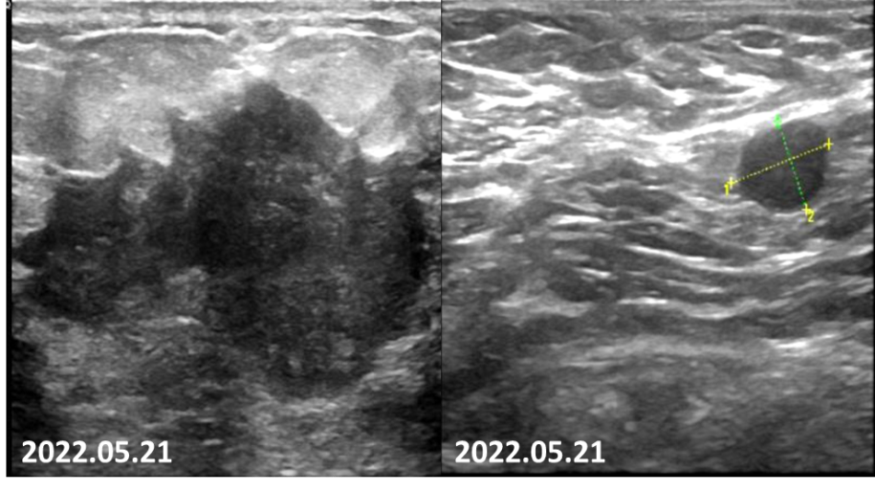

2022-05-21乳腺超声报告:左乳可见多处低回声结节,较大者位于12点钟,大小约47mm×27mm×35mm,距体表10mm,距乳头35mm,形态不规则,边缘成角,内回声不均匀。CDFI:内可及点状血流信号。左侧腋窝可见数个淋巴结回声,髓质消失,较大者大小约12mm×8mm,CDFI:内可见点状血流信号。右侧腋窝及双侧锁骨上窝未见明显肿大淋巴结。

图2.患者乳腺彩超可见肿瘤毛刺征明显,呈浸润性生长,腋窝淋巴结形态失常。

疗效评估:2疗程后,患者肿瘤明显减小,PR。

2022-07-08乳腺MRI报告:左乳上方象限病变可见明显强化,边界不清,大小约24mm×30mm×21mm(上下径×左右径×前后径),病变前缘距乳头约34mm,后缘距离胸壁约11mm。右乳约11点钟方向病变可见明显强化,边界不清,直径约9mm,病变前缘距乳头约50mm,后缘距离胸壁约32mm。左侧腋窝淋巴结肿大,最大直径约8mm。

图4.2疗程后患者左侧乳房肿物退缩明显,强化程度减低。

2022-07-08乳腺超声:左乳可见多处低回声结节,较大者位于12~1点钟,大小约20.6mm×6mm×18.3mm,距体表12mm,距乳头26mm,形态不规则,边缘成角,内回声不均匀,CDFI:内可及点状血流信号。左侧腋窝可见数个淋巴结回声,髓质消失,较大者大小约18mm×8mm,CDFI:内可见点状血流信号。右侧腋窝及双侧锁骨上窝未见明显肿大淋巴结。

图5.2疗程后可见患者左侧乳房肿物仅余核心部分,左腋窝淋巴结形态已接近正常。